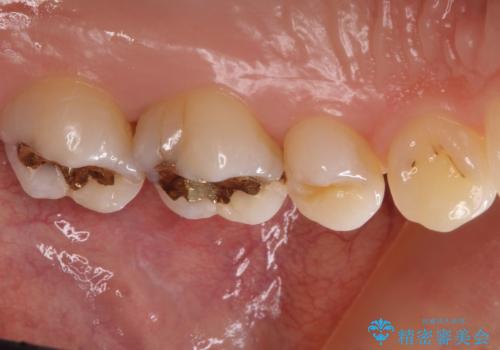

ゴールドインレーを除去し、その下で広がっていた虫歯をきれいに取り除きました。

一度治療した歯も再び虫歯になる可能性があるので、定期的なチェックが大切になります。